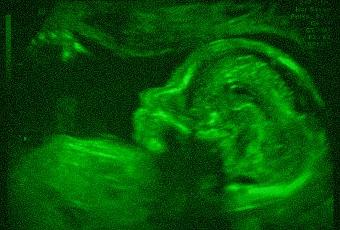

Bonne âme, j'ai quand même poussé l'honnêteté jusqu'à récupérer une photo de vrai martien (enfin, un alien... ), faut pas déconner non plus...